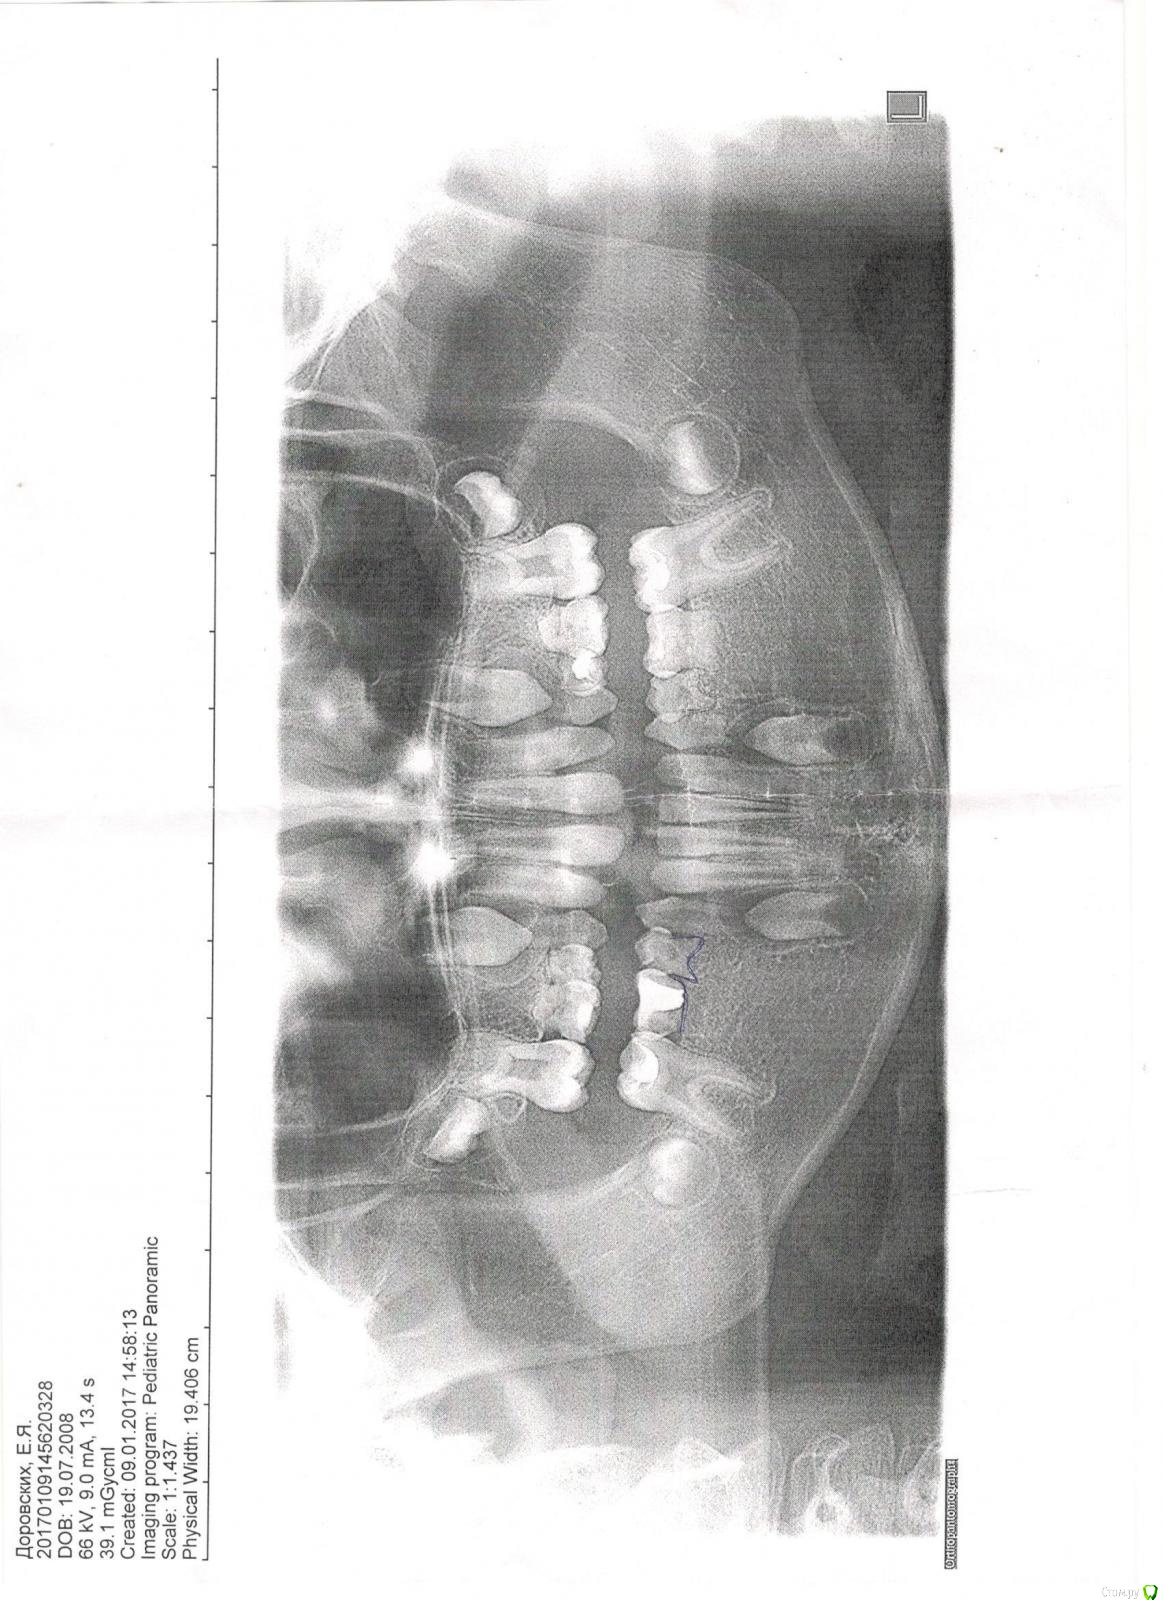

Анализирующая Опубликовано 20 июля, 2017 Поделиться Опубликовано 20 июля, 2017 Здравствуйте. У ребенка отсутствуют зачатки 8 постоянных зубов. Зубы-молочные уже сильно шатаются. Есть ли смысл, необходимость , как только выпадут молочные зубы(те что без зачатков) начать носить брикеты с целью 6ки подвинуть вперёд на месте 5ок, из за этого 7ки подвинуться тоже вперёд. Останутся дырки на месте 4ок и тут поставить имплантанты в 19 лет ? Или только съёмные протезы носить до 19 лет, до имплантантов? Ссылка на комментарий

Анализирующая Опубликовано 23 июля, 2017 Автор Поделиться Опубликовано 23 июля, 2017 Ребенку 9 лет. Молочные зубы, те , что без зачатков подвижны. Врач нам сказала, что очень скоро мы их потеряем и к тому времени мы должны уже выработать план решения проблемы. Очень бы хотелось, чтобы молочные простояли как можно дольше, мы думали, что дотянем с ними до 18 лет. Но недавно еще снимок делали и он разочаровал врача (в плане, что корни молочных имеют динамику к рассасыванию. Ссылка на комментарий